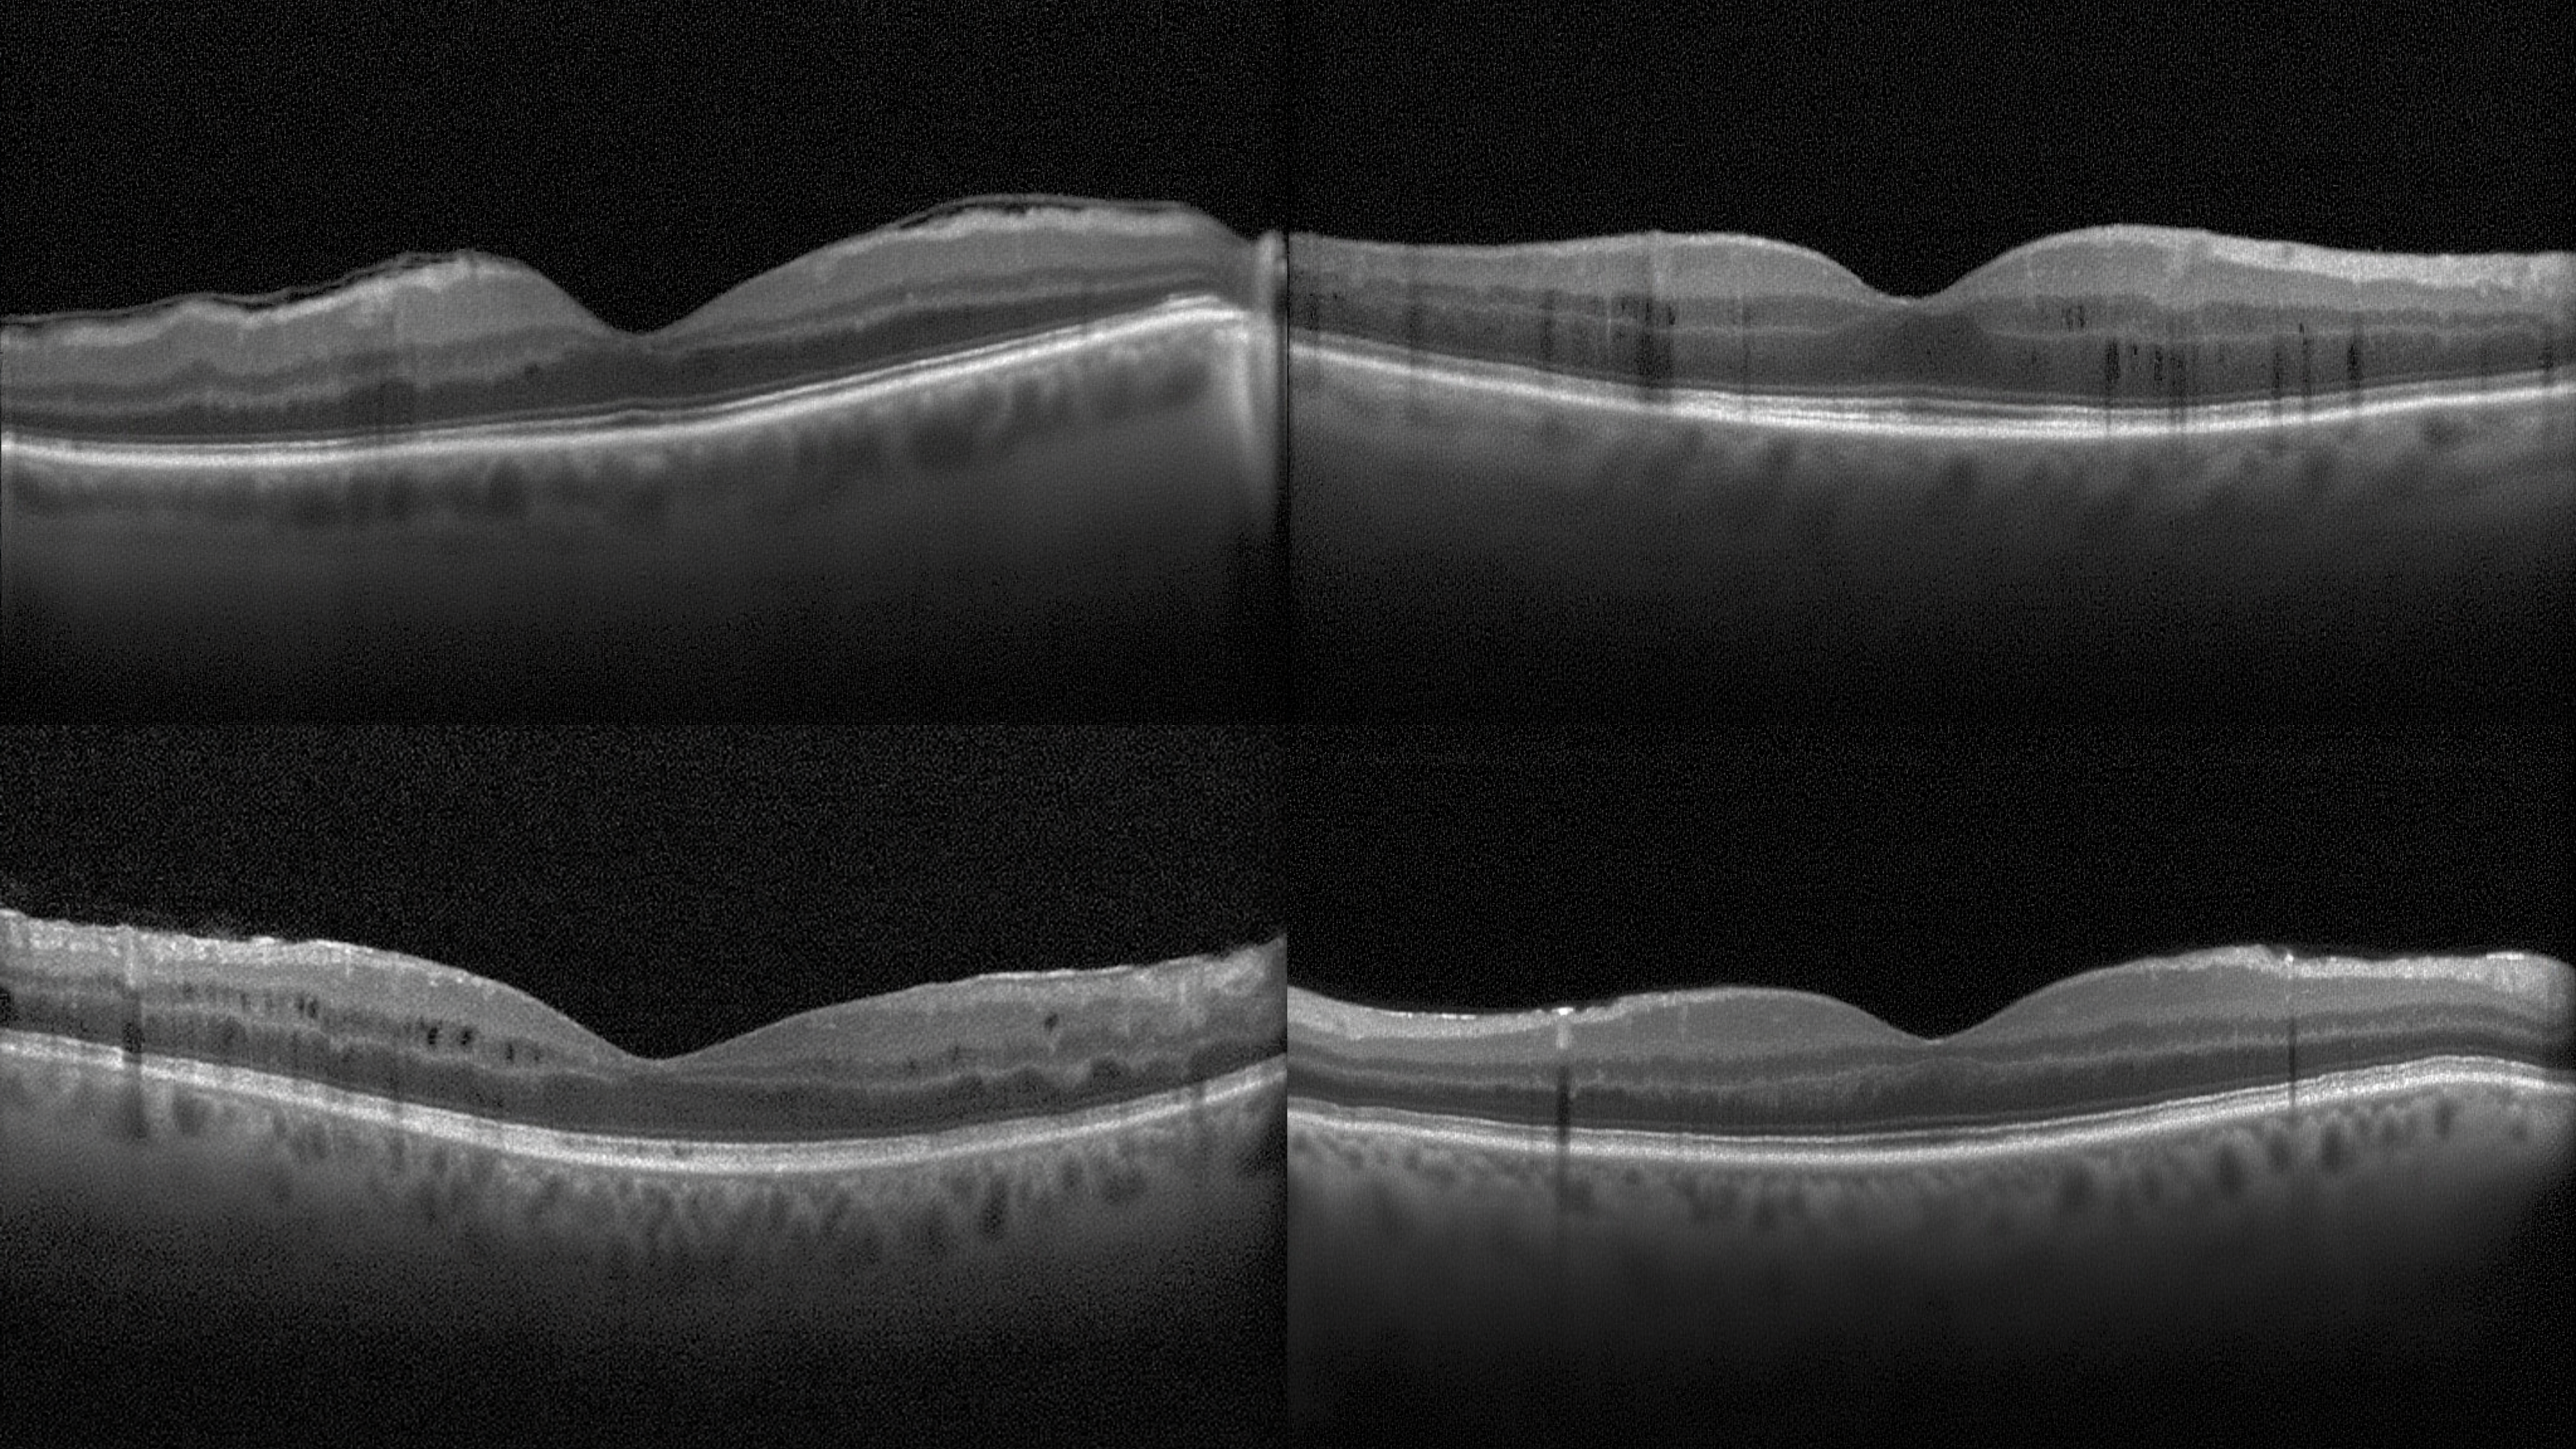

Text-to-medical-image generation results showing high-quality synthesis

Additional text-to-medical-image generation examples across modalities

Medical-Image Generation across 8 modalities

Optical Coherence Tomography (OCT)